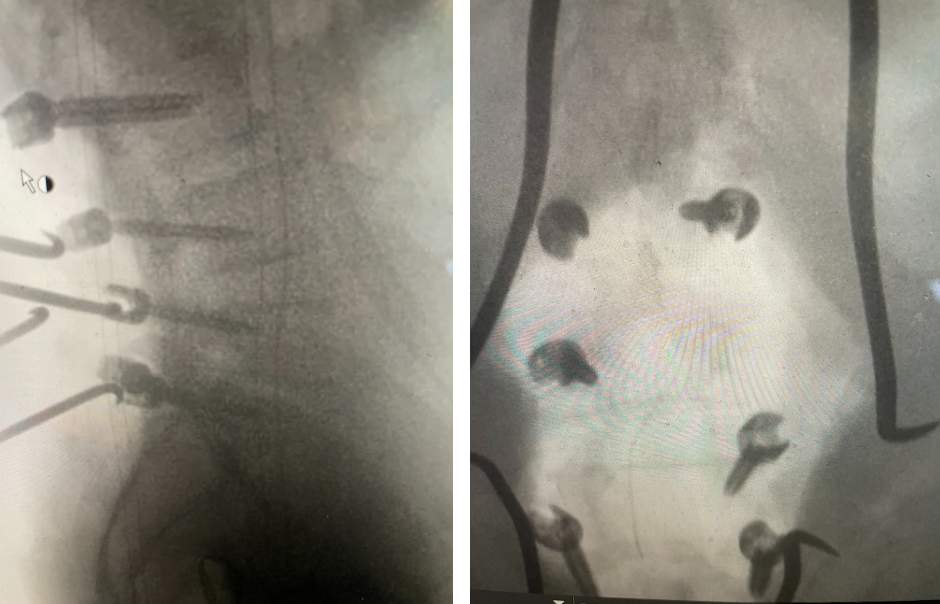

Figure 1. AP lumbar x-ray demonstrating degenerative lumbar levoscoliosis with secondary arthritic changes.

He had mild proximal weakness of his hip flexors. He also had a history of diabetes, hypertension, and hypercholesterolemia. Imaging studies were obtained. Plain x-rays (Fig. 1) demonstrated a degenerative levoscoliosis with the apex of the curve at L2-3. Lumbar MRI (Fig. 2) showed severe degenerative disc disease with an L5-S1 grade 1 spondylolisthesis and a significant retrolisthesis at L3-4 with severe lumbar stenosis.